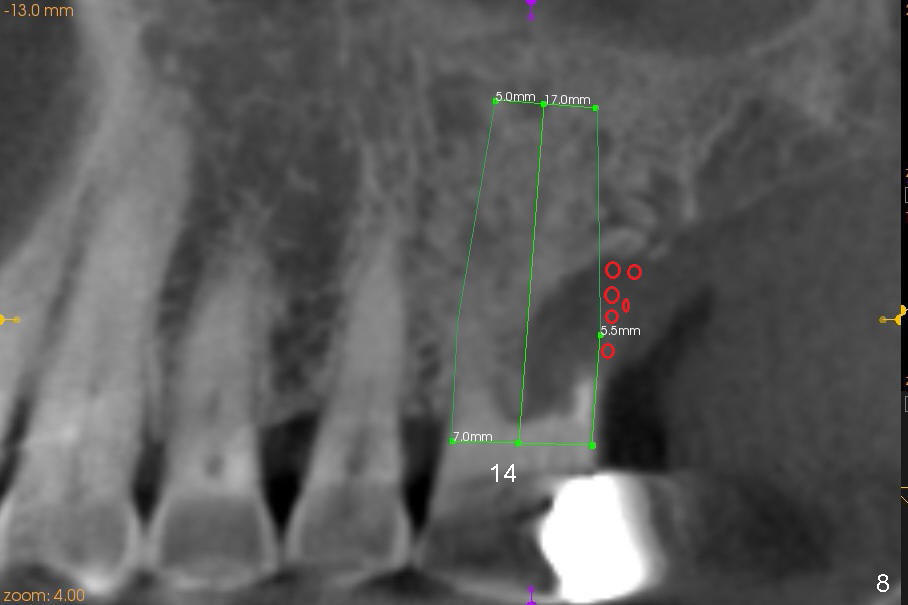

The tooth #14 is periodontally compromised with supraeruption (Fig.8-10). After immediate implant, bone graft (red circles) is needed distally (Fig.8) and palatally (Fig.9).